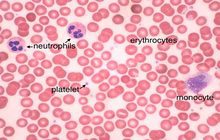

- General and specialized tissue and cell staining

- Prepare educational slides for students from all available tissues

Histological methods includes sample processing in the pathology laboratory, preparation of the slide and its examination under a microscope, sample fixation, molding, microtome cutting, staining and assembly of the slides.